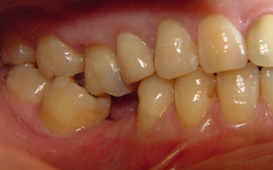

咬合崩塌 / 上牙下墜 / 下牙上長 / 前牙飆出 / 傾倒 / 蛀牙 / 牙周病缺牙未重建 - 臨床實例

上面的牙往下墜,下面的牙往上長,前面的牙往外飆 – 咬合崩塌牙周病,蛀牙;這些現象必然發生,時間越久,問題越大,而且除非藉由矯正及其他牙科治療,無法修正。

缺牙導致牙齒移位 - 臨床實例二